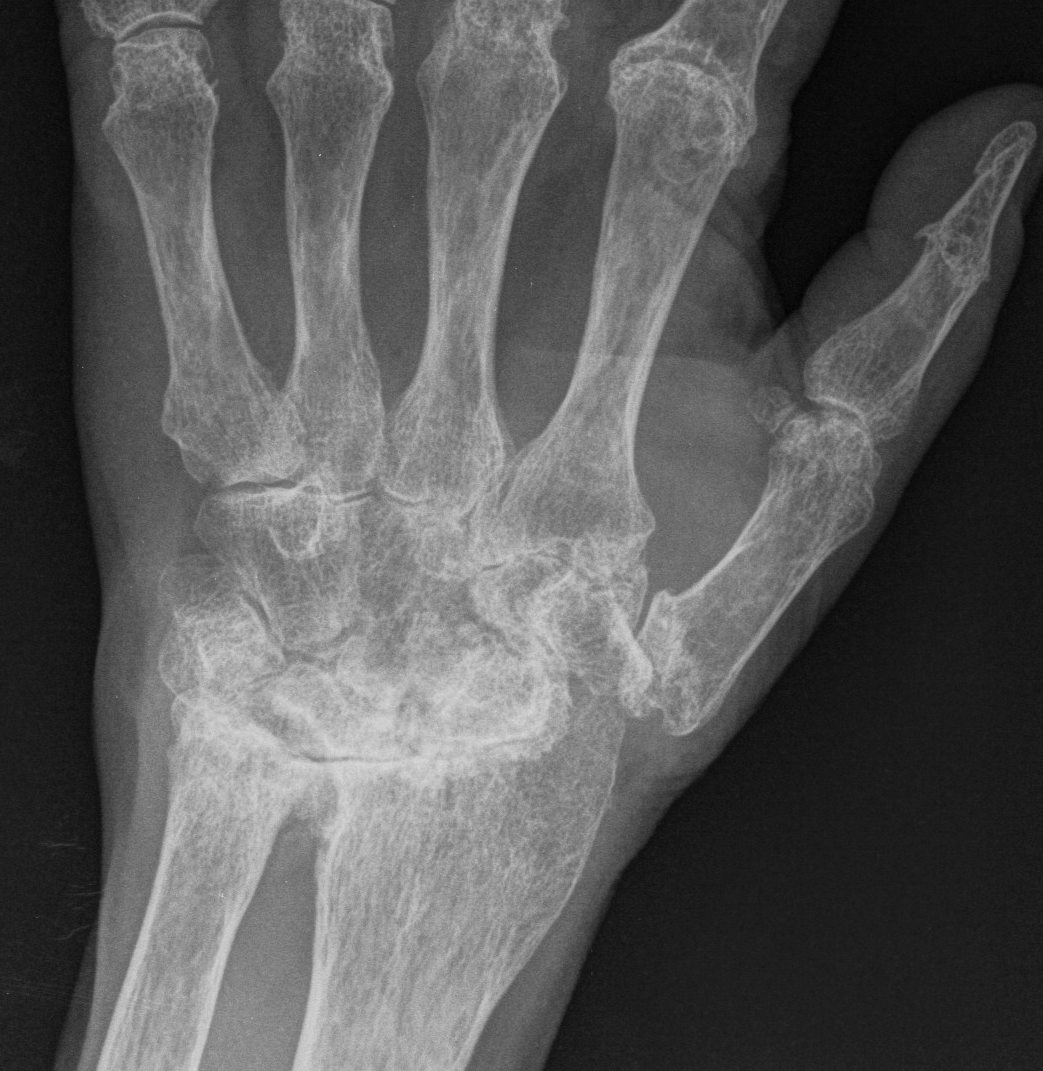

Xray